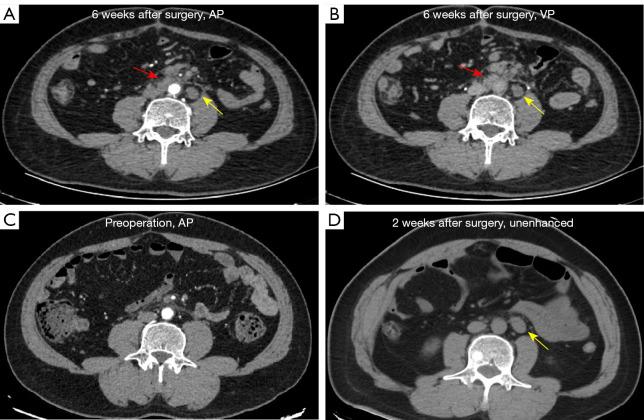

Intraoperative intraperitoneal chemotherapy using sustained-release fluorouracil implants has been used to reduce the recurrence of gastrointestinal tumors. However, these implants may persist and present as tumor-like lesions in imaging studies, potentially leading to false-positive interpretations as metastatic sites, affecting patient management. Our study aimed to enhance the diagnostic accuracy of radiologists in assessing gastric and colorectal cancer patients with fluorouracil implants.

A total of 168 fluorouracil implants were confirmed in the subdiaphragmatic regions, paracolic gutters, and tumor beds of 164 patients. Imaging features such as a typical foreign body reaction (85.71%), no contrast enhancement on CT/magnetic resonance imaging, and no diffusion restriction on diffusion-weighted imaging were important for differentiating between fluorouracil implant-related lesions and malignant lesions. Follow-up CT scans showed a size reduction in 67.26% of the lesions and density changes in 52.98%. The diagnostic accuracy and confidence of the radiologists were improved in stage 2 (accuracy: 91.25%; confidence: most often classified as medium) compared to stage 1 (accuracy: 67.5%; confidence: most often classified as low; both P<0.001). When surgical information was available, the diagnostic accuracy and confidence of the radiologists were improved in stage 3 (accuracy: 100%; confidence most often classified as high) compared to stage 2 (accuracy: P=0.007; confidence: P<0.001).

在164例患者的膈下区域、结肠旁沟和肿瘤床中共确认了168个氟尿嘧啶植入物。典型的异物反应(85.71%)、CT/磁共振成像上无对比增强以及扩散加权成像上无扩散受限等影像学特征对于区分氟尿嘧啶植入物相关病变和恶性病变很重要。随访CT扫描显示67.26%的病变大小减小,52.98%的病变密度改变。与第1阶段(准确性:67.5%;信心:最常分类为低;P均<0.001)相比,放射科医生在第2阶段的诊断准确性和信心有所提高(准确性:91.25%;信心:最常分类为中等)。当有手术信息时,与第2阶段相比,放射科医生在第3阶段的诊断准确性和信心有所提高(准确性:100%;信心最常分类为高)(准确性:P = 0.007;信心:P<0.001)。